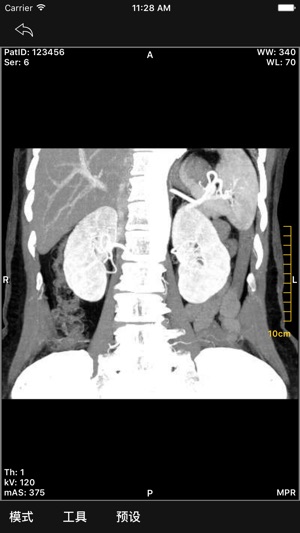

- MPR显示:包括Slab模式查看